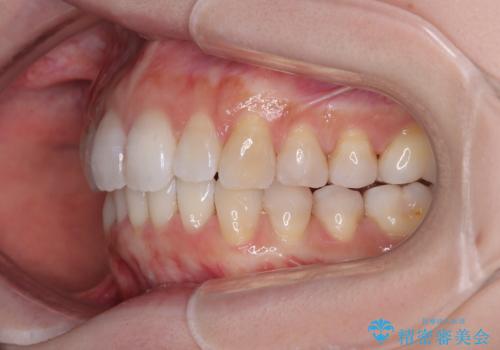

- デコボコと飛び出している前歯を気にして来院された患者様です。

歯列としてはインビザラインでもワイヤー矯正でも対応できるものでしたが、奥歯の咬み合わせを見た時に上顎がやや前方にあり、インビザライン単独では時間のかかってしまう可能性があるため、補助装置を治療当初に使用することで、インビザラインによる治療をスムーズに行えるように計画しました。